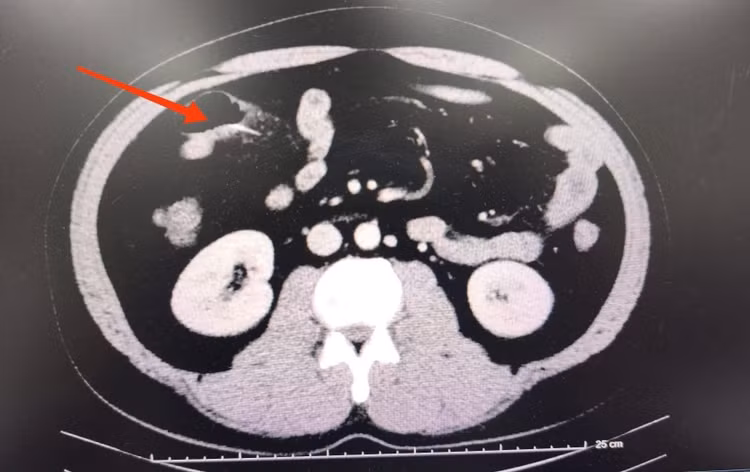

Chụp CT phát hiện một chiếc tăm tre sắc, dài khoảng 3 cm, đâm xuyên thành ruột non gây viêm dày quai ruột.

Ảnh BV